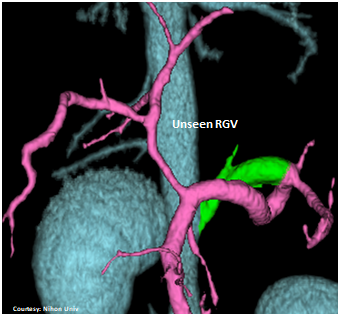

Does the RIGHT GASTRIC VEIN (RGV) contribute blood to the shunt?

WEISSE 2022

slide21

PRE-HEPATIC ENTRANCE

(Absent GSV)